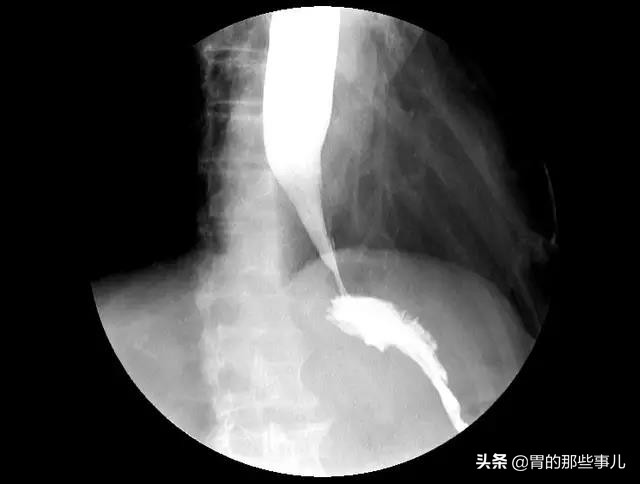

在一次机缘巧合下,张女士发现哮喘竟然和胃有关。做了一系列相关检查后,从检查症状来看,反流还是比较明显的,反流引起的哮喘可能性很大。哮喘是一个呼吸道的疾病,胃食管反流是一个消化系统疾病,看起来好像风牛马不相及的两个病症,但是将这个两个病连起来的原因就是贲门。

贲门就像是一个阀门,长在食道和胃之间,当食物进入胃中后,贲门关闭,控制食物和胃酸不会逆流而上进入食管。贲门出现松弛就会引起胃酸反流,反流出来的胃酸就有可能进入呼吸道。人的呼吸道非常脆弱敏感,有时候喝水突然吸到冷空气都会刺激气道,引起呛咳。何况是胃酸呢,胃酸是一个腐蚀性、刺激性很强的东西,所以往往这种反流引起哮喘,都是重症哮喘,病人随时有生命危险。